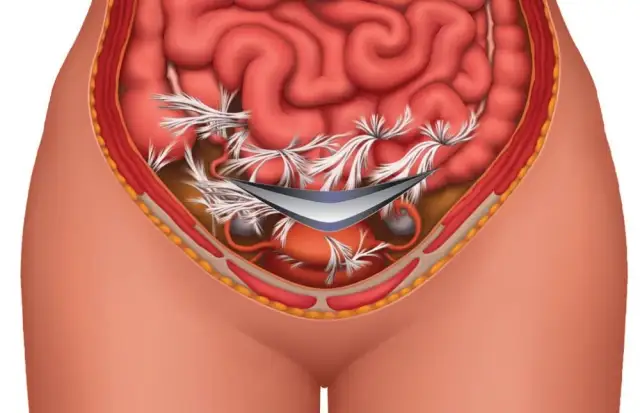

Skuteczne metody i domowe sposoby, aby pozbyć się bólu brzucha. Dowiedz się, jak naturalnie złagodzić dyskomfort i poprawić samopoczucie.

Dowiedz się, jak wywołać ból brzucha i jakie są jego poważne konsekwencje zdrowotne. Poznaj zdrowe alternatywy radzenia sobie z dyskomfortem.

Poznaj objawy bólu brzucha ze stresu oraz skuteczne metody jego łagodzenia. Zadbaj o swoje zdrowie i komfort już dziś!